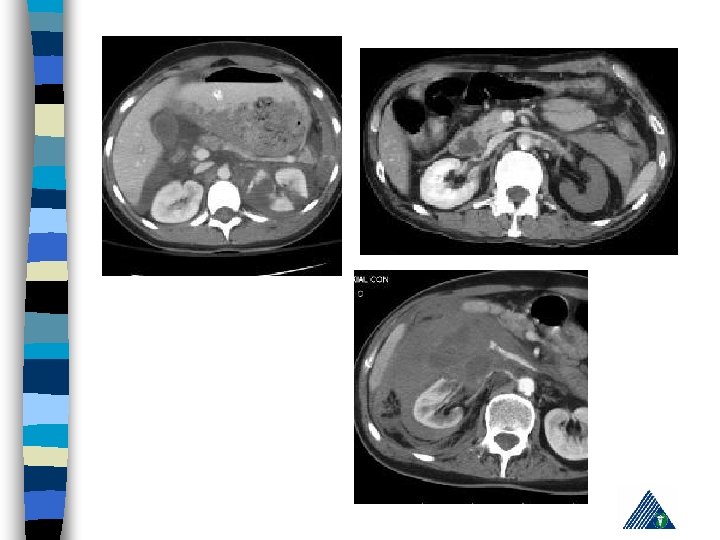

Renal Trauma n Blunt : (85 -90% ) – vehicle accident, fall, rapid deceleration, iatrogenic n Penetrating : Gunshot and (85 -90 % associated with intraabdominal or thoracic injury)

Renal Trauma - Diagnosis History n PE (lumbar echimosis, pain with palpation) n Hematuria n – (Renal vascular injury - 36 % not associated with hematuria) n Variable clinical presentation (asymptomaticshock)

Radiologic Imaging n n n KUB (loss of psoas or renal contour) IVU (delayed renal function, nonhomogenous collecting system) USG (lumbar hematoma and urinoma lokalizasyonu) Computerized Tomography Renal angiography

American Association for the Surgery of Trauma Organ Injury Severity Scale for the Kidney Grade Tip Tanım 1 kontüzyon Mikroskobik ya da gross hematuri, ürolojik incelemeler normal hematom Sub. Kapsuler, genişlemeyen parankimal hasar yok hematom Genişlemeyen perirenal hematom , renal retroperitona sınırlı laserasyon <1 -cm derinlikte parenkimal korteks hasarı, üriner ekstravazasyon yok 3 laserasyon >1 -cm derinlikte parenkimal korteks hasarı, üriner ekstravazasyon yok 4 laserasyon Medulla ve toplayıcı sisteme ulaşan parenkim hasarı vasküler Renal arter ve vende hemoraji içeren hasar laserasyon Tamamen parçalanmış Böbrek vasküler Renal hilusun ayrılması 2 5

Expectant Management: n Hemodynamically stable, well defined and non-expanding injury on CT scan n 88 % patienst are observed n If there is associated gross hematuria, admit and observe

Surgery : Absolute Indication – Persistant renal bleeding – Expanding perirenal hematoma – Perirenal hematoma with pulsation n Relative indication – Urinary extravasation – Inability in proper staging – Delayed arterial injury – Canlı olmayan doku varlığı n